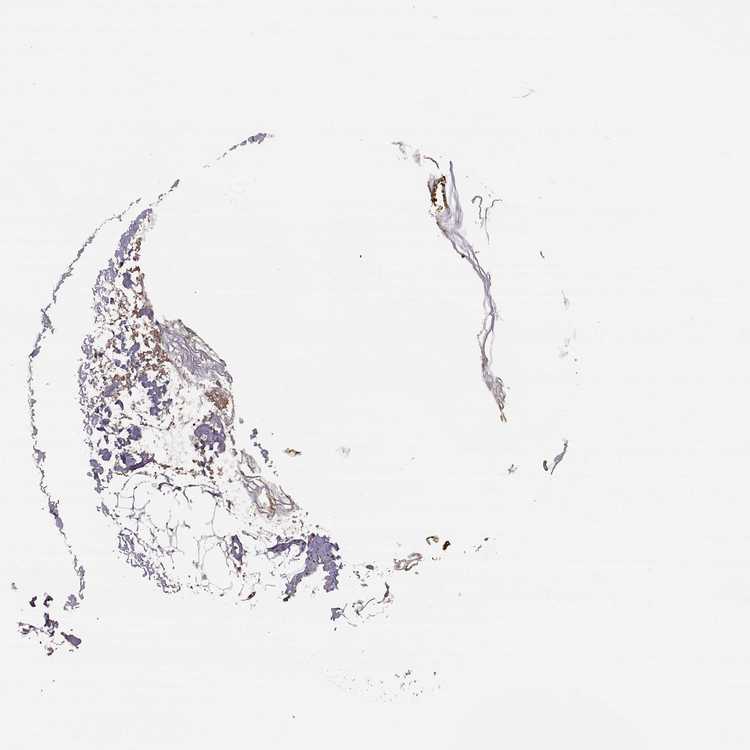

SKIN 2 - Antibody stainingi

Antibody staining in the annotated cell types in the current human tissue is reported as not detected, low, medium, or high, based on conventional immunohistochemistry profiling in selected tissues. This score is based on the combination of the staining intensity and fraction of stained cells.

Each image is clickable and will lead to virtual microscopy that enables deeper exploration of all samples and also displays staining intensity scores, fraction scores and subcellular localization as well as patient and tissue information for each sample.

Antibody HPA069022

Epidermal cells Medium